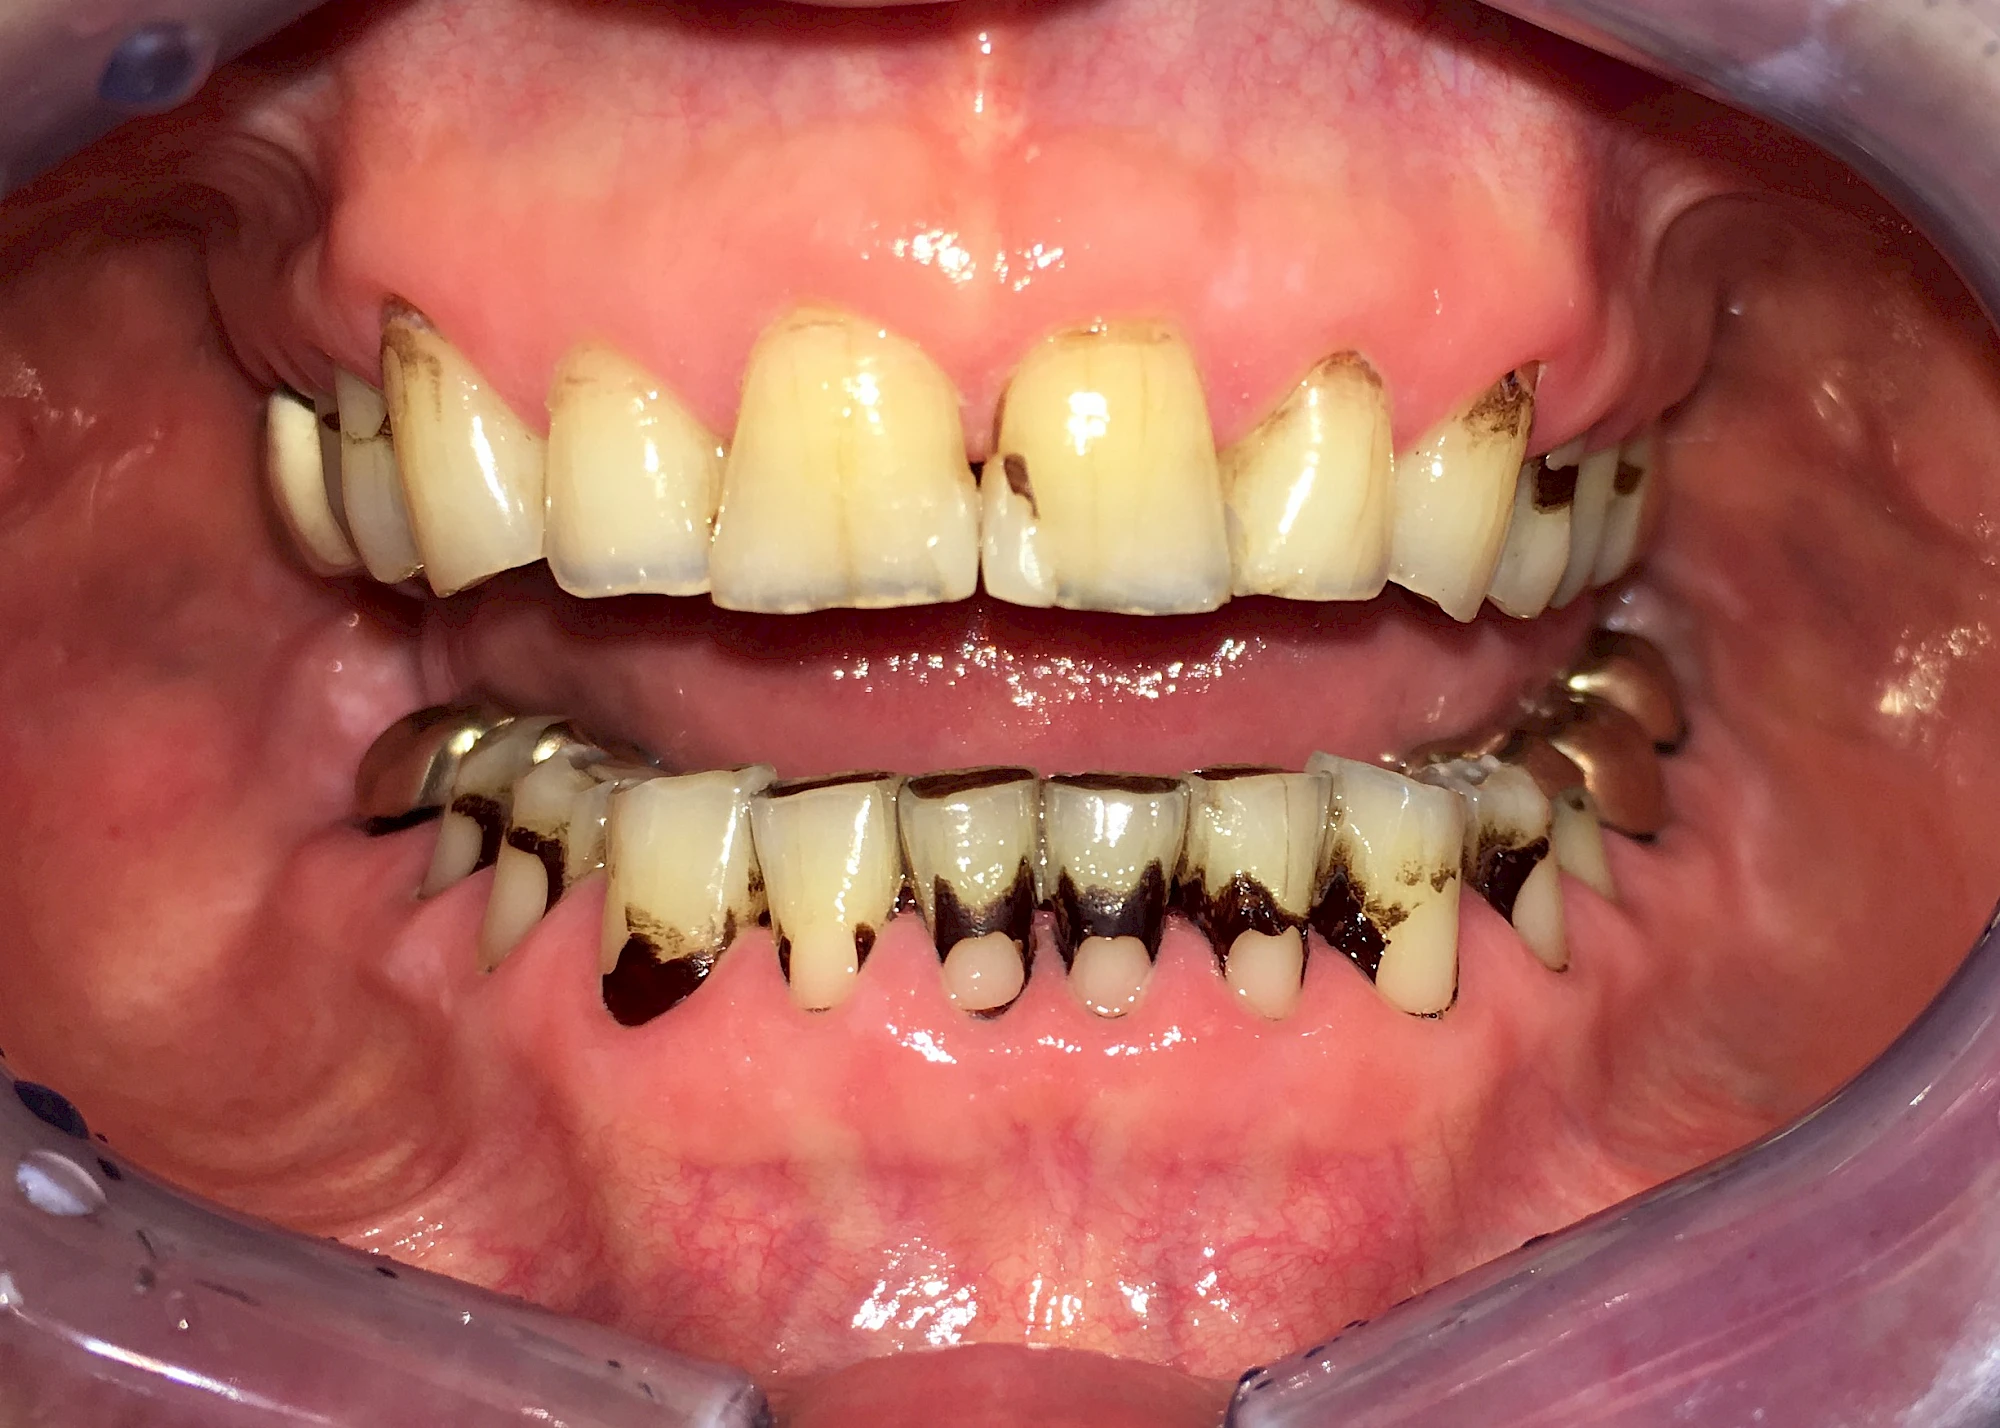

- Genußmittel (Tee, Kaffee, Rauchen)

- Medikamente (z. B. Eisen)

Äußere Verfärbungen durch Genußmittel oder Medikamente (Eisen!) lassen sich meist nur durch den Zahnarzt z. B. mit einer professionellen Zahnreinigung entfernen.

Manche Medikamente wie zum Beispiel das Antibiotikum Tetrazyklin kann bei Einnahme im Zeitfenster der Zahnentwicklung auch irreversibel in die Zahnsubstanz. eingelagert werden. Tetrazyklin verfärbt die jeweils betroffenen Zähne bläulich und sollte deshalb während der Schwangerschaft und bei Kindern nicht verordnet werden.